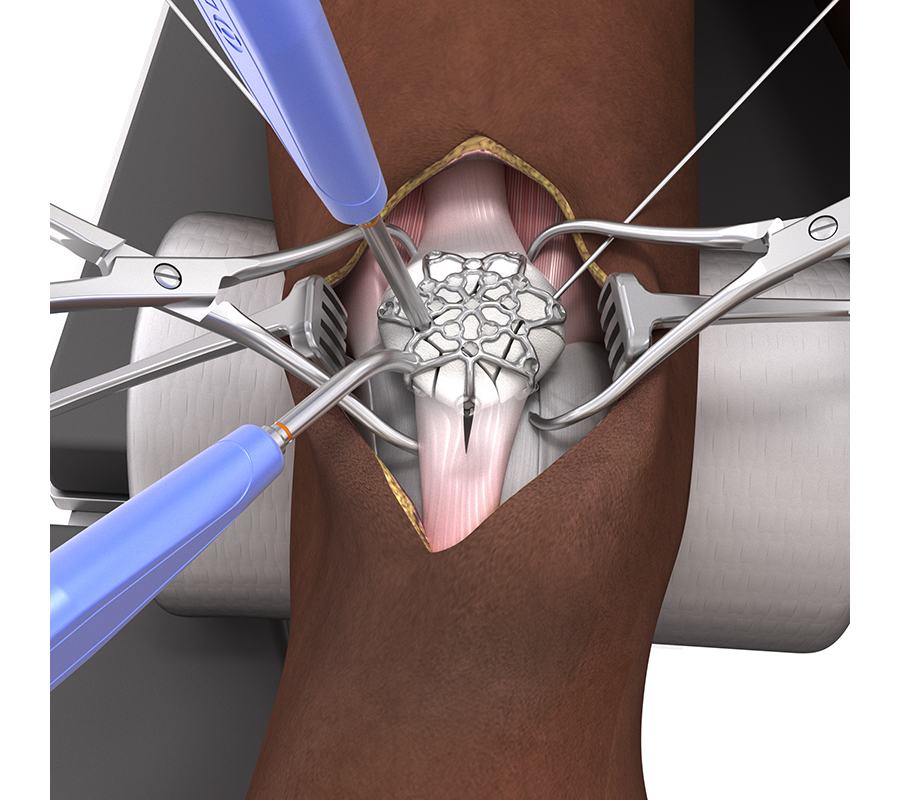

The surgical technique which was refined throughout several anatomy labs (Fig 6) comprises the following steps:

2. Create a midline or parapatellar incision (a lateral parapatellar incision is recommended to preserve the inferomedial blood supply).

3. Reduce the fracture fragments (with reduction forceps and K-wires). It can be beneficial to evert the patella to achieve accurate fracture reduction and joint congruency under direct vision (Fig 7).

In most complex fractures a three-hole or six-hole plate is useful for bending the plate legs around the rim of the patella to basket and fix bone fragments. The plate can be oriented on the patella as needed to utilize the plate legs for fracture fixation. For distal to proximal screw placement through the distal patella pole (with a pole screw) a longitudinal split in the patellar tendon is required to insert the plate leg. Sometimes proximal to distal screw placement through the quadriceps tendon might be preferred. The VA locking or cortex screws can be used as pole screws (Fig 8). It is important to place the pole screw(s) before the insertion of the anterior to posterior locking screws.

2.4/2.7 Variable Angle Locking Lateral Rim Patella Plates